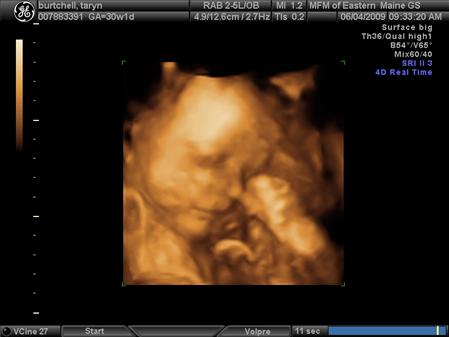

DH and i had our 3rd Level II 3D ultrasound and got to see baby Lauren again. She is doing great. Her left kidney has improved to normal developmental status and her right kidney is just under the cut-off to be considered normal, so it looks like her kidneys will be just fine. We go back in 6 weeks instead of 4 just to double check since it will be 3 weeks before she is due to arrive. She is 3.5 pounds exactly and is actually measuring a little on the big side, they said she is measuring in the 53rd percentile. She is still currently head down, basically in birthing position and has turned into a little gymnast with both feet by her head. The ultrasound tech said "it looked like she was picking her nose with her big toe" which you can see in one of the pictures. She has some shubby little cheeks!! And she has hair, DH and i weren't expecting that because we were both very bald babies so we are excited for some hair too!!

The first picture is the one with her big toe by her nose. I also added a new belly pic since i haven't taken one in a while. Image Attachment(s):